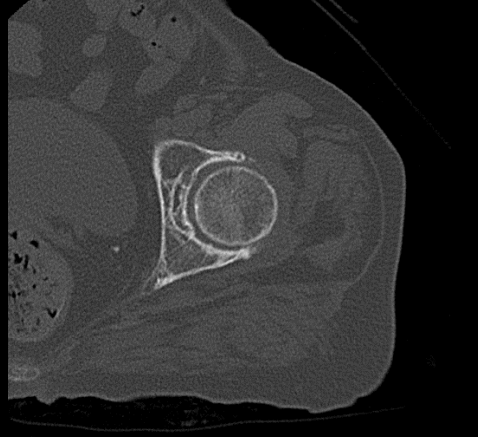

A tomografia computadorizada articular é um exame de diagnóstico por imagem de alta qualidade que, como o próprio nome indica, é realizado para analisar as articulações. No corpo humano, as articulações fazem parte do sistema articular e são responsáveis pelos diversos movimentos que realizamos. Uma articulação conecta ossos a outros ossos e cartilagens. São exemplos de articulações: joelho, ombro, cotovelo, punho, tornozelo, coxofemoral, temporomandibular, entre outros.